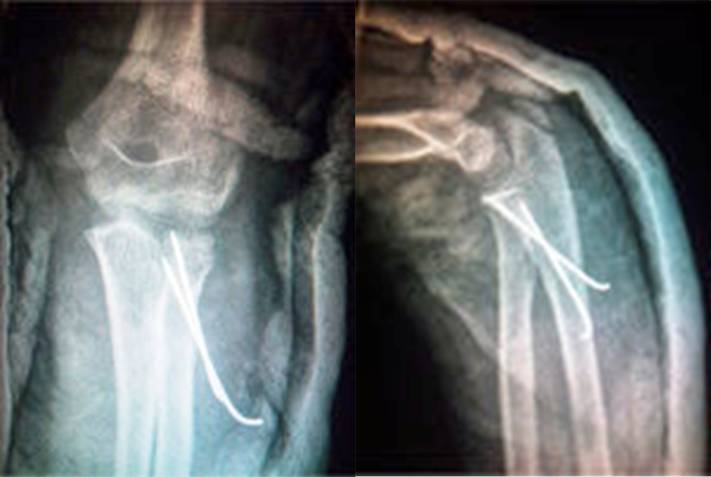

顺行固定

逆行固定

虽然不推荐贯通肱骨小头与桡骨头,有时候可能比较容易获得稳定

(下图摘自湖南省儿童医院伍江雁医生课件图片

如果可能,克氏针放在非关节面的安全区域更好,Caputo 和他的同事推荐用桡骨茎突与 Lister 结节对应的这个近端范围为内植入物的安全区域。